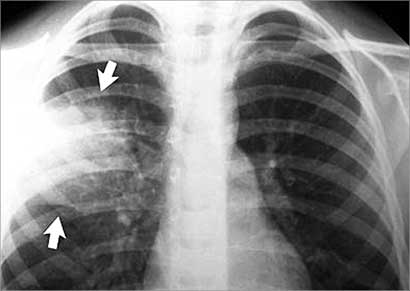

الالتهاب الشعبي والرئوي من مضاعفات السعال الديكي

من مضاعفات السعال الديكي الاصابة بالالتهاب والالتهاب الرئوي خصوصاً بعد فترة تتراوح بين ثلاثة إلى خمسة اسابيع من بداية المرض ويكون مصحوباً بارتفاع شديد في درجة الحرارة مع زرقة وشحوب في الوجه وصعوبة في التنفس مع ازدياد في ضربات القلب وأحياناً حدوث تشنجات.